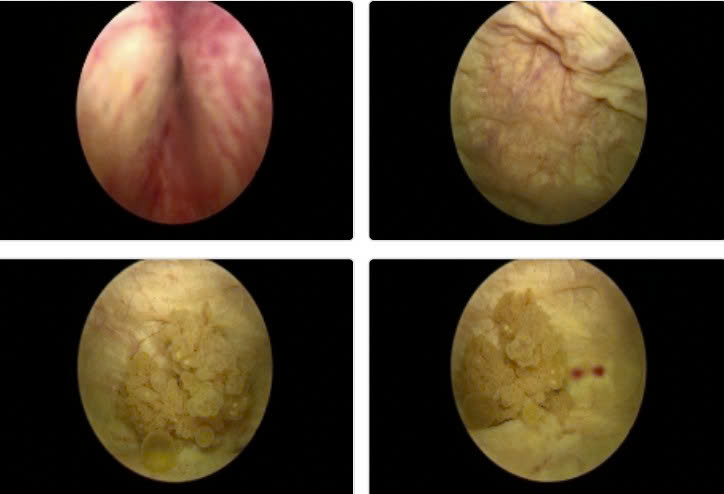

Chiến lược thông minh phối hợp liên chuyên khoa được ekip thống nhất: Thay vì mổ mở cắt hai u thì tổ chức phẫu thuật nội soi bàng quang ngược dòng cắt u. Sau hai ngày thì chuẩn bị để cắt khối tá tụy nội soi hoàn toàn.